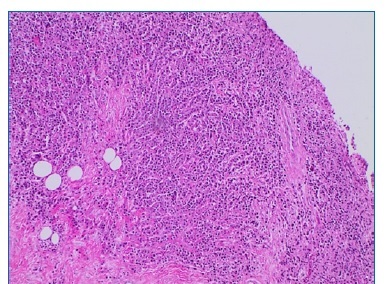

Além disso, não foi diagnosticada lesão mandibular no primeiro episódio. A paciente comunicou que omitiu o diagnóstico durante a anamnese por não acreditar ter relação com a odontalgia, e por ter feito exames laboratoriais e de imagem de corpo inteiro que descartaram qualquer sinal do mieloma, há cerca de trinta dias. Realizou-se punção aspirativa por agulha fina da área entumecida, não sendo observado presença de material líquido, sendo então optado pela realização de biopsia incisional (Figura 4), sob anestesia local, devido a necessidade de conclusão do diagnóstico. Durante o procedimento cirúrgico foi possível evidenciar um nódulo de superfície lisa, brilhante, avermelhada com estrias esbranquiçadas e friável a manipulação. A análise histopatológica (Figuras 5, 6 e 7), corada com Hematoxilina e Eosina, revelou proliferação de células de morfologia plasmocitóide, que apresentavam atipia, cromatina nuclear pontilhada e invasão do tecido conjuntivo, conferindo o laudo de mieloma múltiplo, sem necessidade de marcação imunohistoquímica, devido ao diagnóstico dessa lesão no passado.

Figura 5 Lencol de plasmocitos invadindo tecido conjuntivo fibroso (x100 - coloracao com Hematoxilina e Eosina)